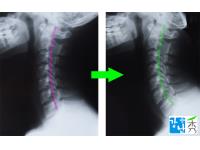

• 교정전후사진